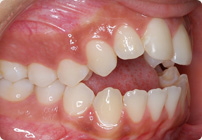

Femenino

Antes

Despues

Caso: 19 años

Adulto: Clase III

Mordida Abierta Anterior

Mordida Cruzada Anterior y Posterior

Endo necesitado para #19

Extract U5’s, LR4, LL6

6 alambres superiores

5 alambres inferiores

Elásticos Clase III 2oz. TP Verde

Retenedores: Interior Fijo de TMA y Hawley en superior

Tiempo de tratamiento: 21 Visitas